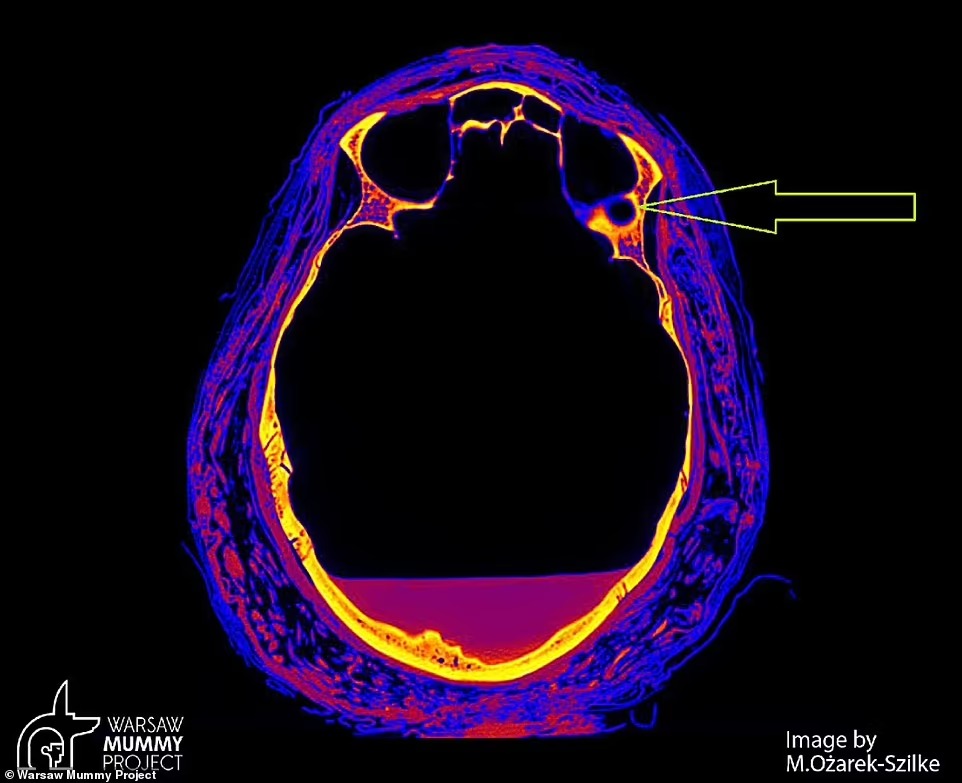

ووفقًا لصحيفة ديلي ميل البريطانية، فإن صاحبة المومياء ماتت بسبب نادر من المرض، حيث مر على حملها نحو 28 أسبوع، وأجرى باحثون من بولندا، مسحًا لجمجمة الجثة للمرأة المصرية القديمة، عندما اكتشفوا علامات غير عادية في العظام.

وتُظهر الصور الصادرة عن مشروع وارسو مومياء WMP في بولندا، أن الجمجمة المصابة بآفات على الأرجح، ناتجة عن ورم وعيوب كبيرة في أجزاء من العظام، لا تتشكل عادةً أثناء إجراءات التحنيط.

وقال الدكتور رافاي ستيك من قسم الأورام بجامعة وارسو الطبية، وقائد البحث: لدينا تغيرات غير عادية في عظام البلعوم الأنفي، مع حدوث تغييرات في ورم بالعظام.